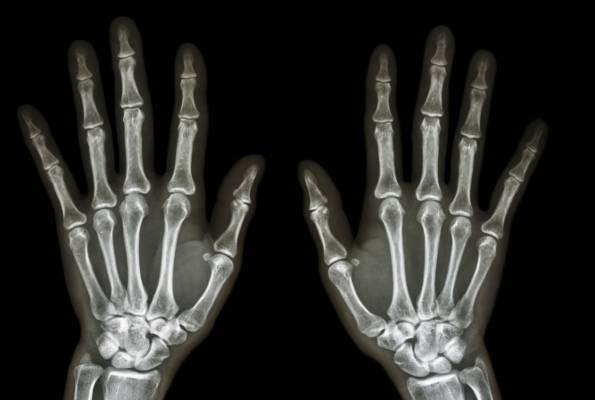

Osteomijelitis (upala kostiju)

Kod djece, osteomijelitis najčešće utječe na duge kosti noge i nadlaktice, dok je kod odraslih veća vjerojatnost za razvoj osteomijelitisa u kostima koje čine kralježnicu (kralješci). Ljudi koji imaju dijabetes mogu razviti osteomijelitis u kostima nogu, ako su im stopala inficirana.

Putem krvi - klice u drugim dijelovima tijela; na primjer, od upale pluća ili infekcije mokraćnog sustava - mogu putovati kroz krvotok do oslabljenog mjesta na kosti. Kod djece se osteomijelitis najčešće javlja u mekšim područjima, na oba kraja dugih kostiju ruku i nogu.